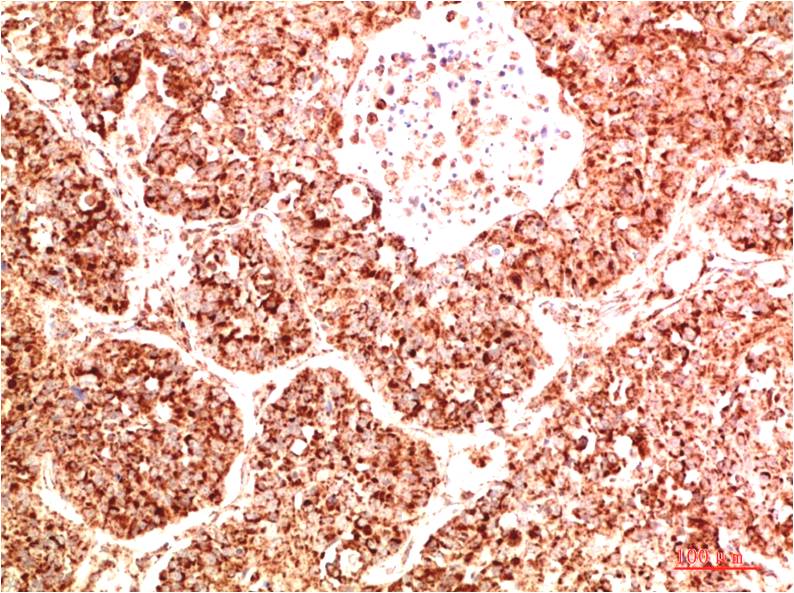

IkB α Rabbit Polyclonal Antibody

Applications :WB, IHC

| Recommended dilutions: | WB 1:500-2,000 IHC 1:50-300 |